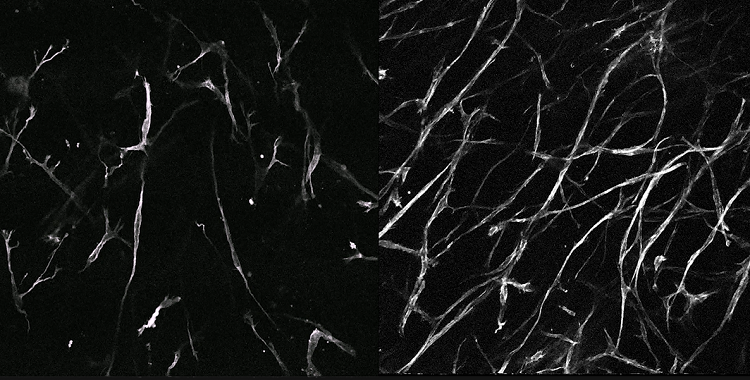

4、自体荧光OptiScan成像

左:ACL中有序的胶原纤维;右:ACL中过度负荷后的无序胶原纤维。

注:前交叉韧带(ACL)的自体荧光成像。本研究着眼于疲劳相关微损伤导致的前交叉韧带失效。Scale bar=100μm。